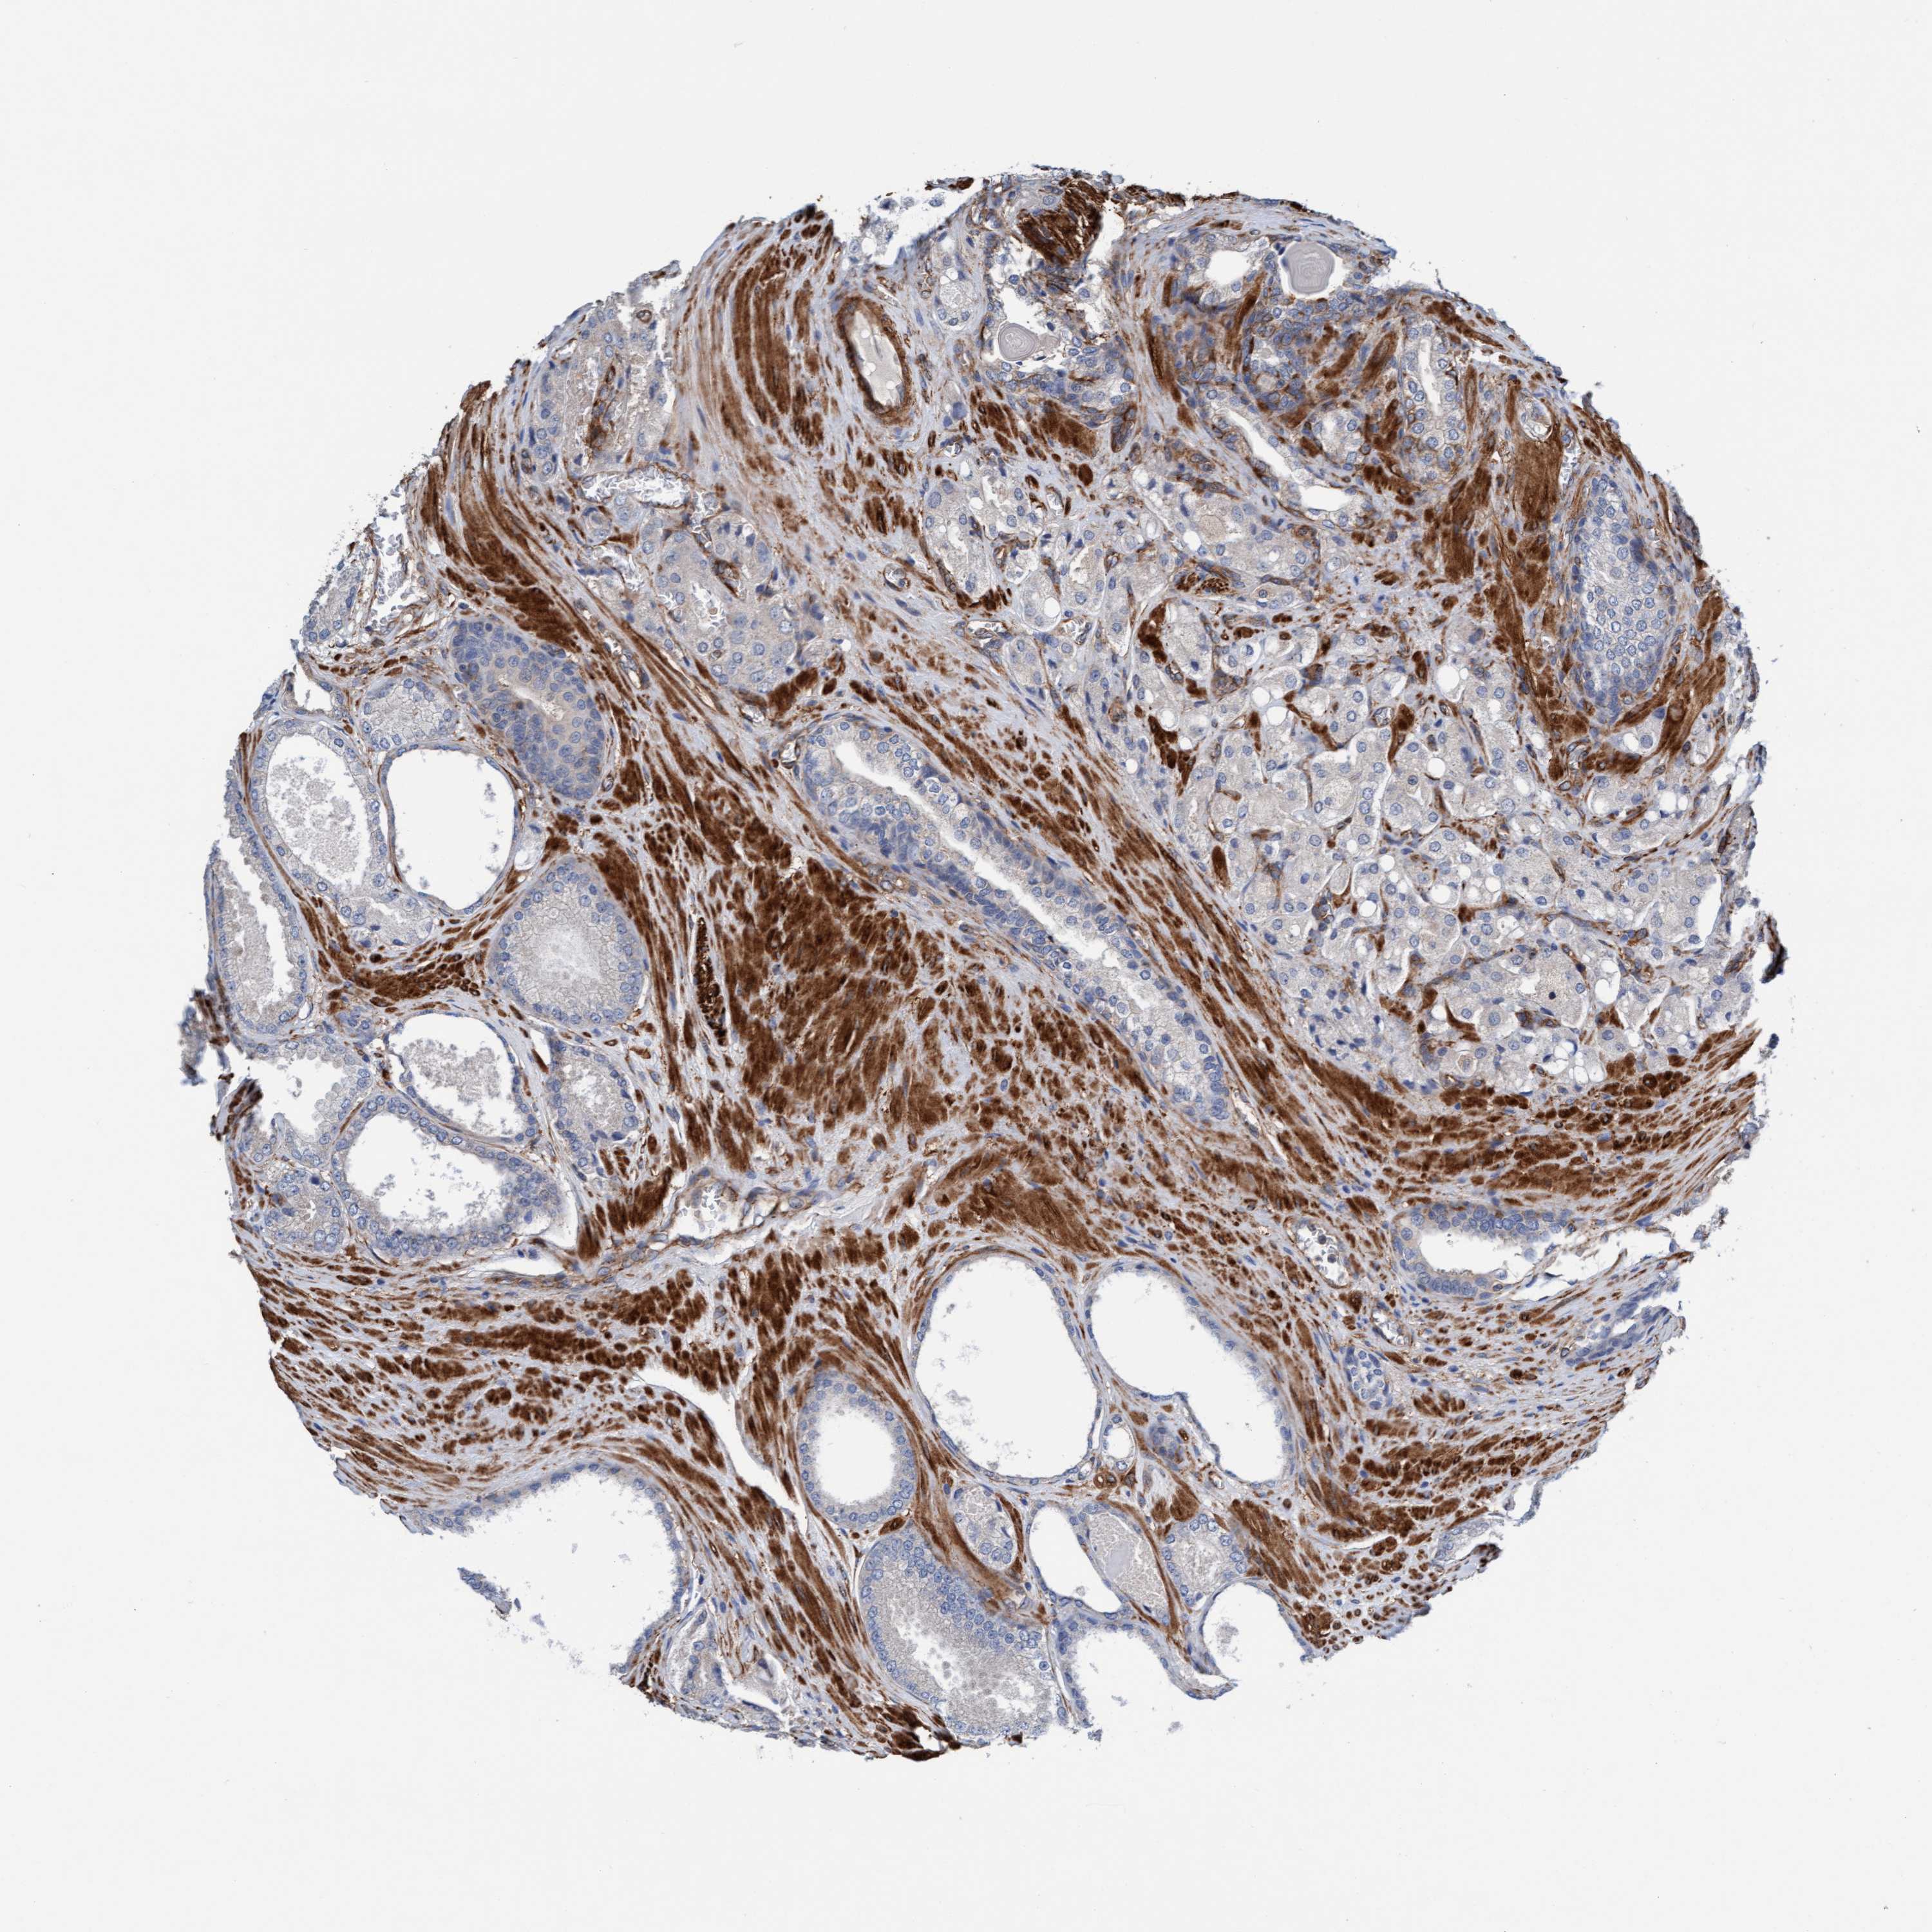

PROSTATE CANCER - Protein expressioni

A mouse-over function shows sample information and annotation data. Click on an image to view it in a full screen mode. Samples can be filtered based on level of antibody staining by selecting one or several of the following categories: high, medium, low and not detected. The assay and annotation is described here.

Antibody stainingi

Antibody staining in the annotated cell types in the current human tissue is reported as not detected, low, medium, or high, based on conventional immunohistochemistry profiling in selected tissues. This score is based on the combination of the staining intensity and fraction of stained cells.

Each image is clickable and will lead to virtual microscopy that enables deeper exploration of all samples and also displays staining intensity scores, fraction scores and subcellular localization as well as patient and tissue information for each sample.

Antibody HPA002552

Antibody HPA023201

Staining

High

Medium

Low

Not detected

Intensity

Strong

Moderate

Weak

Negative

Quantity

>75%

75%-25%

<25%

None

Location

Nuclear

Cytoplasmic/membranous

Cytoplasmic/membranous,nuclear

Adenocarcinoma, Low grade

Adenocarcinoma, Medium grade

Adenocarcinoma, High grade